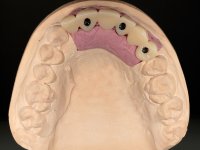

The diagnostic wax-up enclose the possibility to include, or not, gum-shade ceramics to rehabilitate the interdental papillae. This two possibilities were presented to the patient due to the bone regeneration unpredictability (in our opinion), mainly vertically.

The wax-up allowed us to do a mock-up that worked also as a radiological template. The CT-scan was imported to an implant planning software where three dental implants were simulated, and a surgical guide developed.

10 weeks after the surgery, a first impression was done to do a CAD-CAM provisional bridge (based on the diagnostic wax-up), that worked the soft tissue architecture during two months. This architecture was copied in a second impression by individualizing the impression copings in their emerging profile.

The working model was scanned and the dental technician developed a zirconia framework based on the diagnostic wax-up. This framework try-in was done, the perfect fit was assessed, and a final impression was done with a light silicone.